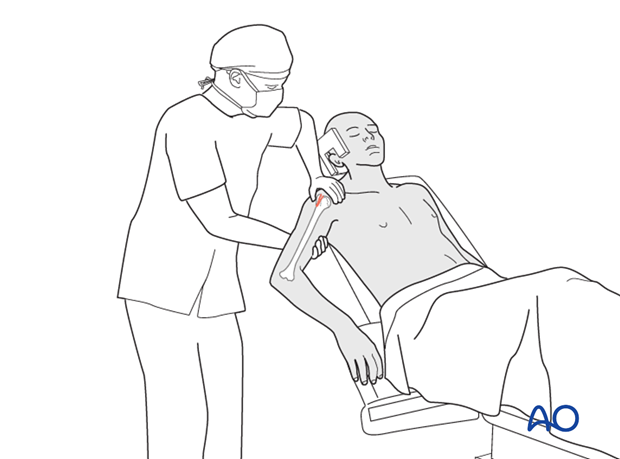

This illustration depicts a patient positioned in the beach chair configuration, which is standard for most shoulder procedures, including fixation of greater tuberosity fractures.